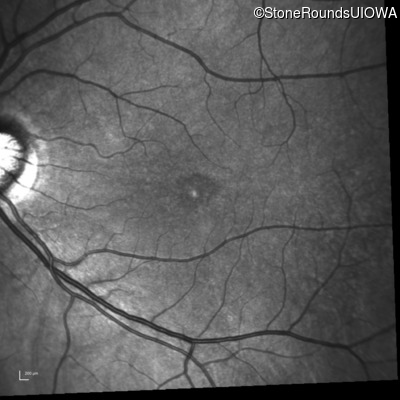

Infrared Fundus Photograph - Left - 20/40

Exemplar